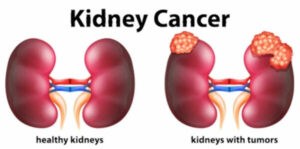

سرطان الكُلى نمو خلايا يبدأ في الكليتين. الكليتان هما عضوان بشكل حبة الفاصولياء وكل منهما بحجم قبضة اليد تقريبًا. وتقعان خلف أعضاء البطن؛ كل كلية